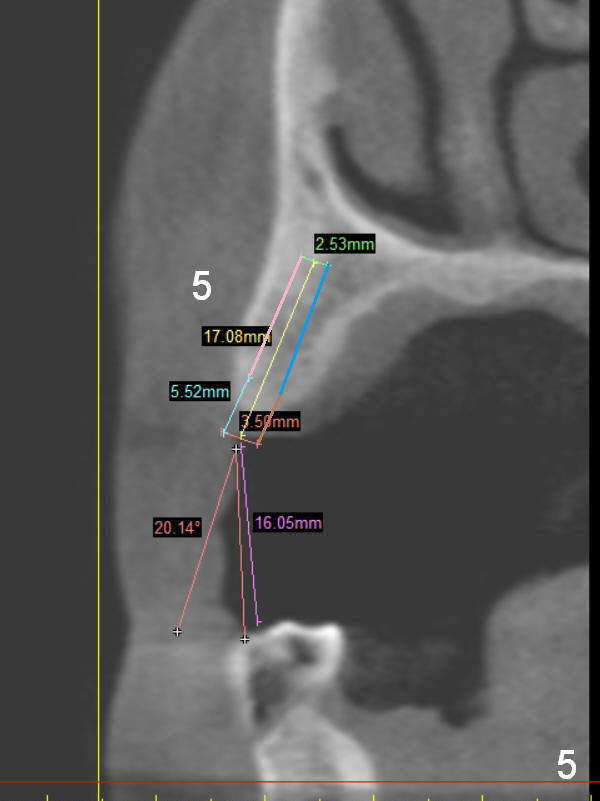

A 68-year-old lady has several missing teeth (Fig.1,2). She has agreed to have an implant at the site of #3 (Fig.3) to stabilize an upper removable partial denture (RPD). The latter will be more stable if an extra implant is placed at #6 (Fig.1,2,6). There is enough bone to place implants at #4,5 (Fig.4,5). Bone density at these sites is low. Osteotomy should be underprep with bone condensation. Edentulous space is high so long abutments are required (9 mm instead of 3 or 5 mm (regularly used)). Angled abutments should be prepared.